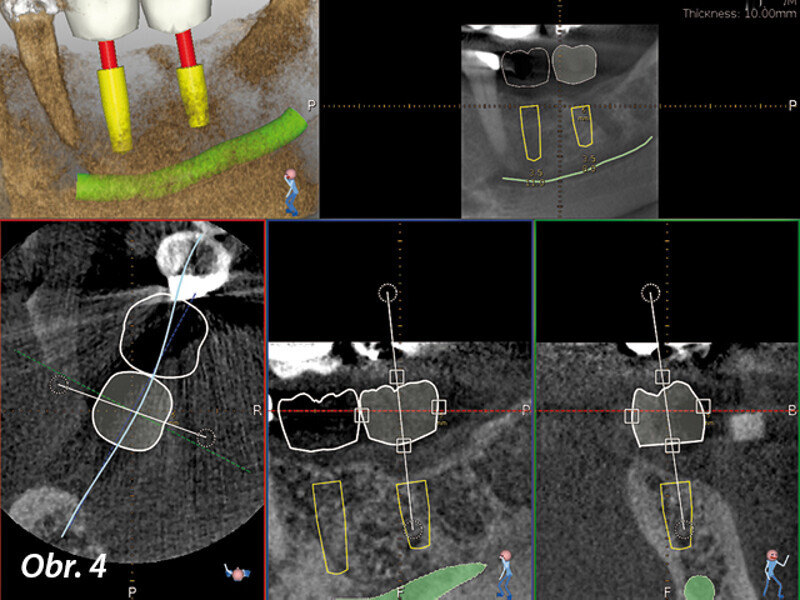

Dynamická navigace pro přesnou implantaci v případech kritické anatomie